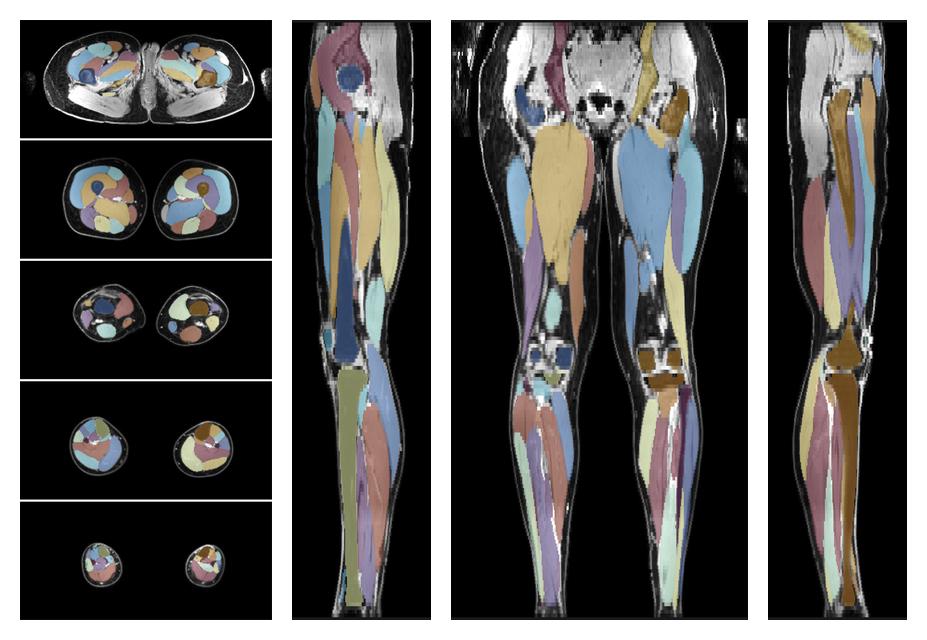

Muscle segmentation

Convolution neural network based (UNET) fiber automated muscle segmentation, for information look here».

• Automated muscle and bone segmentation.

Overlay of automated muscle segmentation labels on dixon water image.